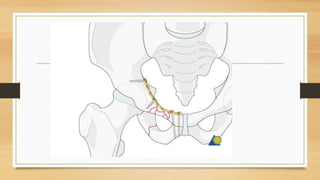

Este documento trata sobre fracturas de pelvis y acetábulo de tipos I y II. Explica la anatomía de la pelvis, incluyendo huesos, ligamentos y vasos. Describe la epidemiología, clasificación y diagnóstico de fracturas de pelvis. Detalla abordajes quirúrgicos, técnicas de osteosíntesis y fijación externa para el tratamiento de fracturas de pelvis. Finalmente, cubre posibles complicaciones.